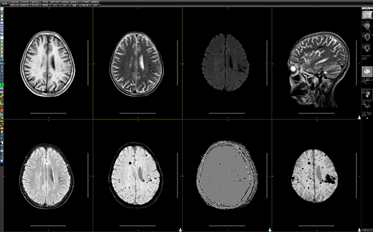

图⑨ 磁共振SWI功能成像对微小出血检出及颅内型海绵状血管瘤检出。